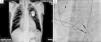

Apresentamos o caso de uma mulher de 80 anos, portadora de pacemaker definitivo modo VDD desde 2001 por doença do tecido de condução sintomática que foi submetida a substituição do gerador por exaustão do mesmo em fevereiro de 2009. Em agosto de 2010 recorreu ao serviço de urgência por quadro clínico com 2 meses de evolução e em agravamento progressivo de dispneia de esforço classe iii/iv NYHA, ortopneia, edemas, dor abdominal de predomínio nos quadrantes direitos, astenia e anorexia. Ao exame objetivo apresentava distensão venosa jugular, cianose facial, edemas generalizados, hepatomegalia, pulso periférico irregular e rápido, auscultação pulmonar sem sinais de estase, sons cardíacos hipofonéticos e sopro mesossistólico aórtico e diastólico de baixa frequência no bordo esternal esquerdo. O eletrocardiograma mostrou fibrilação auricular com resposta controlada alternando com ritmo de pacemaker ventricular. A radiografia de tórax revelou cardiomegalia, apagamento dos fundos de saco e um anel redundante do eletrocateter ventricular ao nível do aparelho valvular tricúspide, sem outras alterações relevantes (figura 3A). No estudo analítico foi detetada ligeira elevação do BNP e de γ-GT, sem outras alterações dignas de registo. O ecocardiograma revelou folhetos da VT espessados e eletrocateter ventricular aderente ao aparelho valvular e subvalvular a condicionar limitação grave da sua amplitude de abertura (gradientes máximo e médio de 15 e 10mmHg e área funcional estimada em 0,6 cm2) (figura 4), esclerose aórtica e derrame pericárdico de médio volume ao nível da parede livre do ventrículo esquerdo (1,6cm) e de grande volume na parede do ventrículo direito (2,4-2,1cm) com ligeiro colapso diastólico do ventrículo direito (figura 3B). O cateterismo cardíaco direito mostrou anormal posicionamento do eletrocateter de pacemaker no seu percurso valvular tricúspide e VT deformada, com abertura excêntrica de amplitude reduzida e gradiente médio 11mmHg) (figura 5). O cateterismo esquerdo revelou válvula aórtica deformada e calcificada com gradiente máximo ventrículo-aórtico de 13mmHg, função ventricular esquerda conservada – fração de ejeção de 62%) e coronárias com doença aterosclerótica parietal calcificada sem evidência de estenoses significativas. Transferida para centro de Cirurgia Cardiotorácica, onde após avaliação foi decidido efetuar pericardiocentese evacuadora associada a optimização da terapêutica médica. Dada a evolução sintomática favorável foi proposta terapêutica conservadora com posterior reavaliação da necessidade de intervenção cirúrgica. Seis meses após a alta a doente encontra-se em classe funcional ii/iv NYHA e apresenta ecocardiograma com ET severa e estenose aórtica ligeira, sem derrame pericárdico.

A) Radiografia de tórax a mostrar cardiomegalia, apagamento dos fundos de saco e um anel redundante do eletrocateter ventricular ao nível do aparelho valvular tricúspide. B) Ecocardiograma em modo B a evidenciar derrame pericárdico de médio volume ao nível da parede livre do ventrículo esquerdo (1,6cm) e de grande volume na parede do ventrículo direito (2,4-2,1cm).